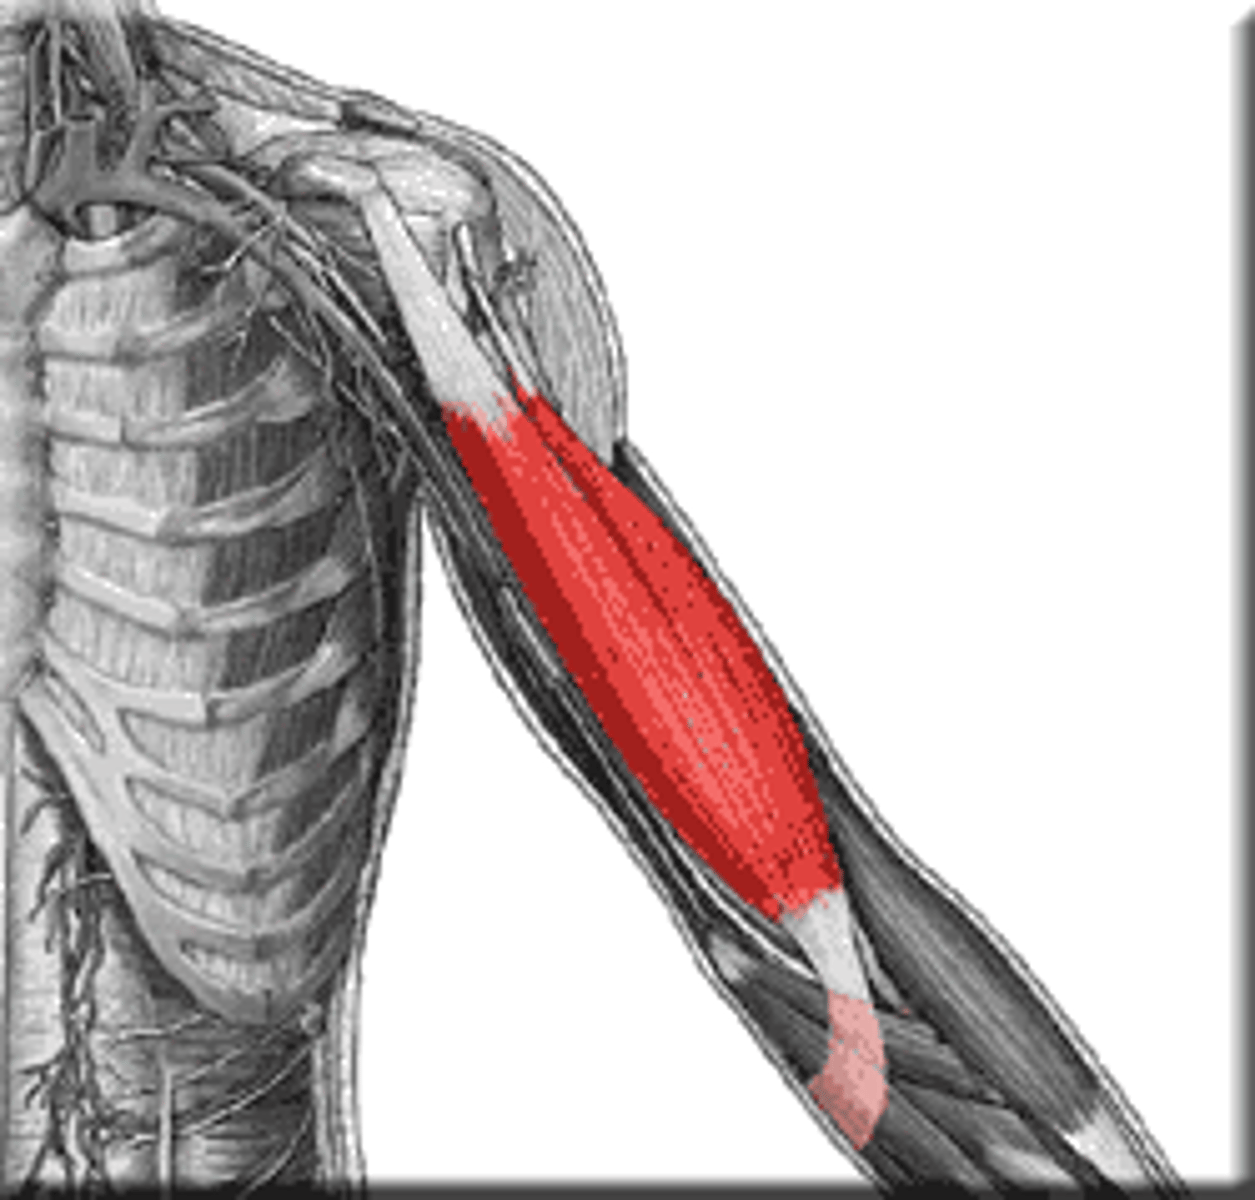

biceps

front of upper arm muscle